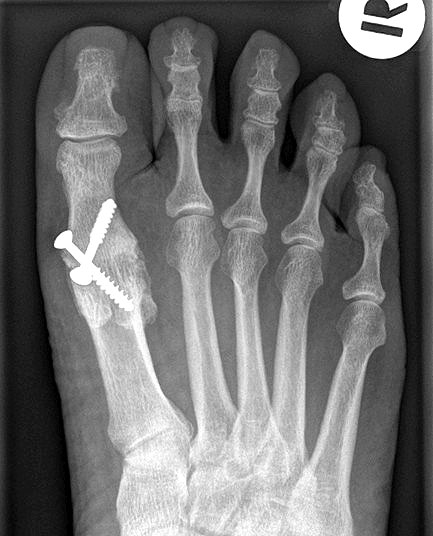

Das nachfolgend präsentierte OP-Verfahren zeigt die Großzehengrundgelenkarthrodese mit Gelenkflächenpräparation mittels sogennanter „Cup-and-Cone“-Fräsen und einer dorsal angebrachten variablen winkelstabilen Platte mit Gleit-/Kompressionsloch.

• Röntgenaufnahmen des Vorfußes (unter Belastung) im dorsoplantaren und seitlichen Strahlengang (Abb. 1a+b)

Gekreuzt eingebrachte Schrauben werden immer noch als kostengünstige Standardtechnik der Osteosynthese beschrieben und können bei kräftigen und stabilen Knochenverhältnissen und entsprechender Erfahrung prinzipiell verwendet werden 141516. Der Einsatz kanülierter Schrauben unter Durchleuchtung erleichtert die Operation.

• Röntgen-Kontrolle der Osteosynthese und Stellung intraoperativ / postoperativ, nach 3 Wochen und nach 6 Wochen